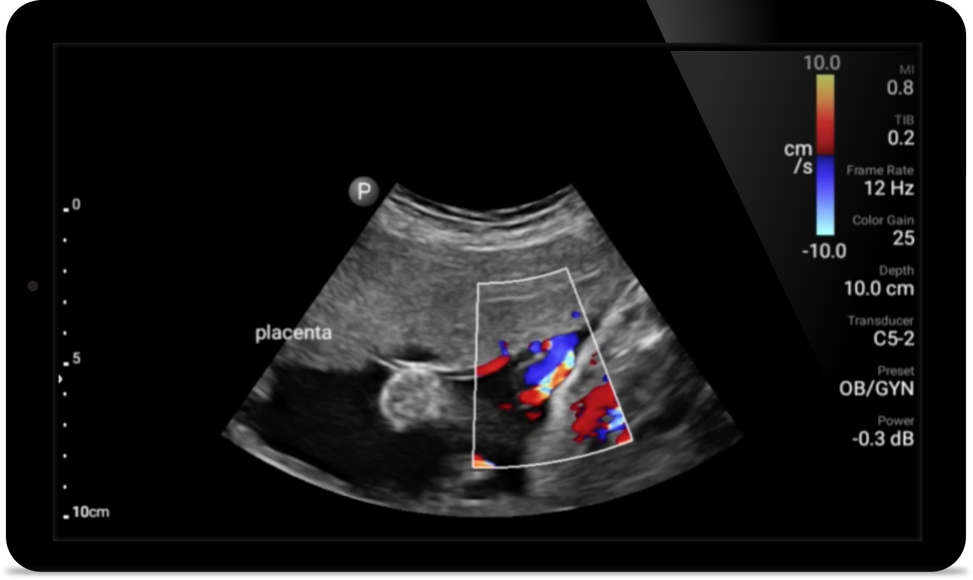

Reduce complications in needle guided procedures

Lumify handheld ultrasound for anesthesiology helps you clearly visualize border definition with your needle placement, surrounding nerves, vessels and fascial planes.

• 4 to 1 MHz extended operating frequency range • 2D, color Doppler, M-mode, advanced XRES and multivariate harmonic imaging • High-resolution imaging for abdominal and cardiac applications: Cardiac, OB/GYN, Lung, Abdomen and FAST imaging preset optimizations